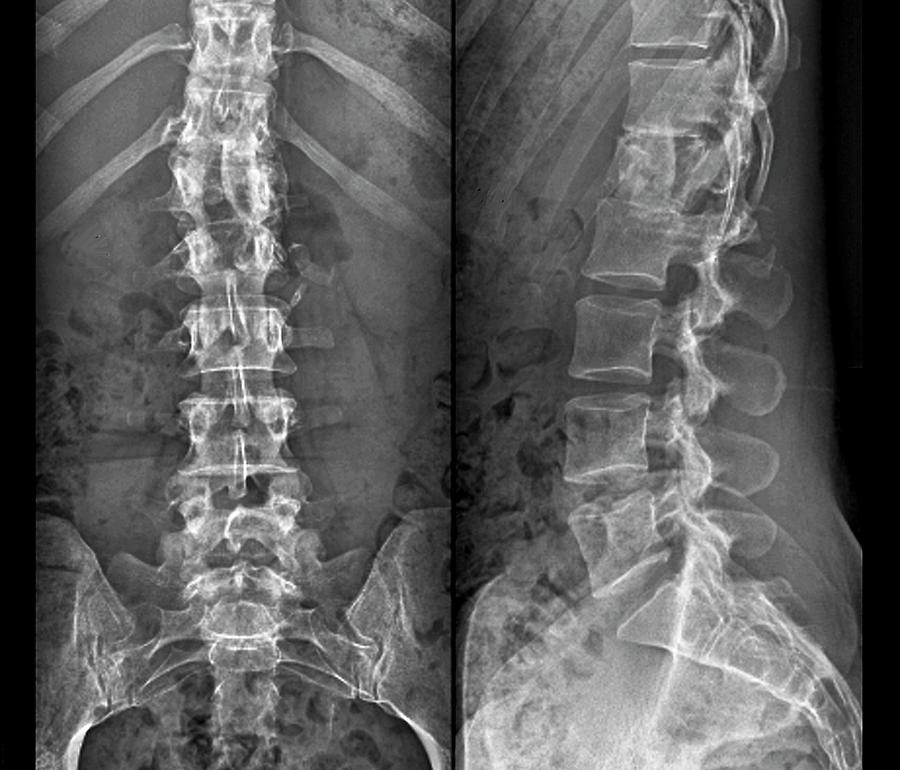

Fractured spine

Fractured spine 140 фотографий